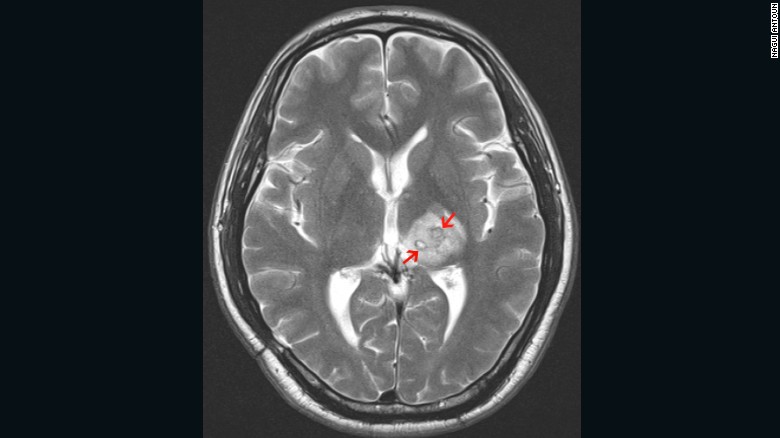

In 2013 a British man of Chinese ethnicity was diagnosed with a tapeworm, Spirometra erinaceieuropaei, inside his brain. The 50-year old was first experienced headaches four years earlier and was treated for tuberculosis. The arrows point to the mass created by the worm in his brain.

After four years, the British patient returned to hospital in pain to find his brain lesion had migrated to a new region of the brain resulting in new symptoms, including seizures. His MRI scans show the tapeworms’s burrowed migration through the brain over four years.

… but infection with worms’ juvenile (larval) form has worse consequences as the younger worms can migrate to other parts of the body. If they enter the nervous system the worms can form cysts in the brain, which have severe consequences, including epilepsy. In the radiology image above, the cysts are identified as white lumps within the brain.